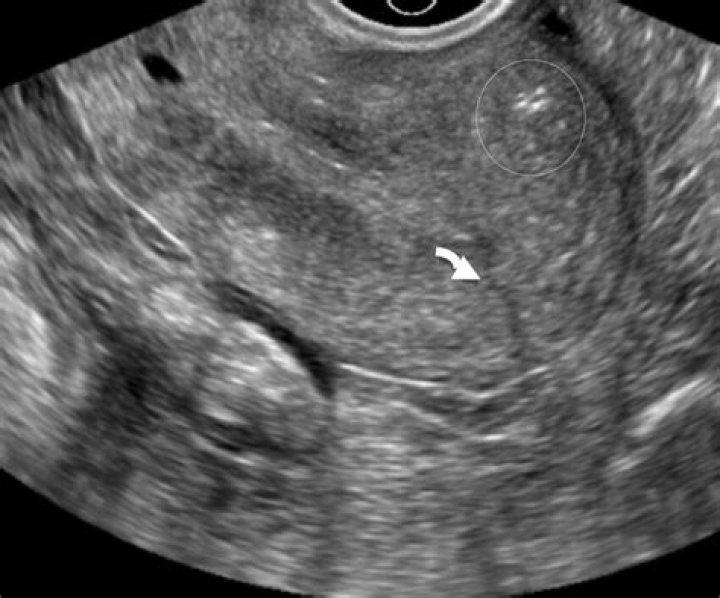

Score: 4.7/5 (30 votes) uterine perforation was defined as full penetration of IUD through myometrium and into the abdominal cavity. perforation occurred...